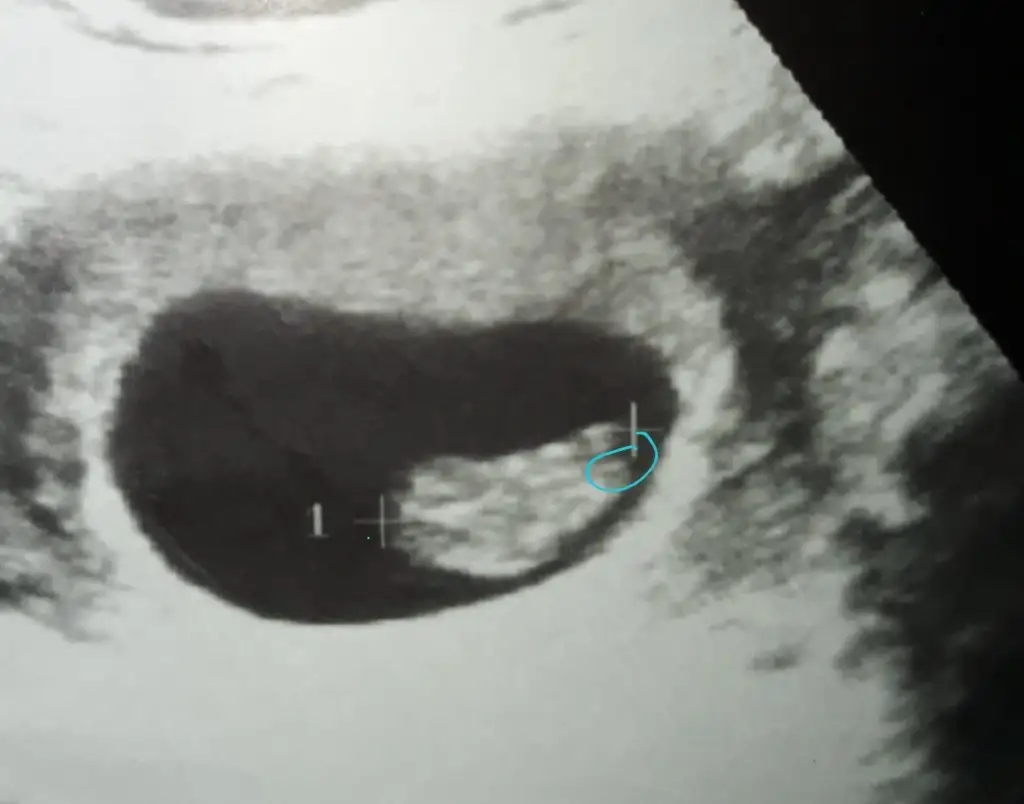

Ikra soruyorum kizma lutfen bu isaretlediklerim nubu degilmi bacagimi acabaYolk saç solda görünüyor

Hayır nub olmazIkra soruyorum kizma lutfen bu isaretlediklerim nubu degilmi bacagimi acaba